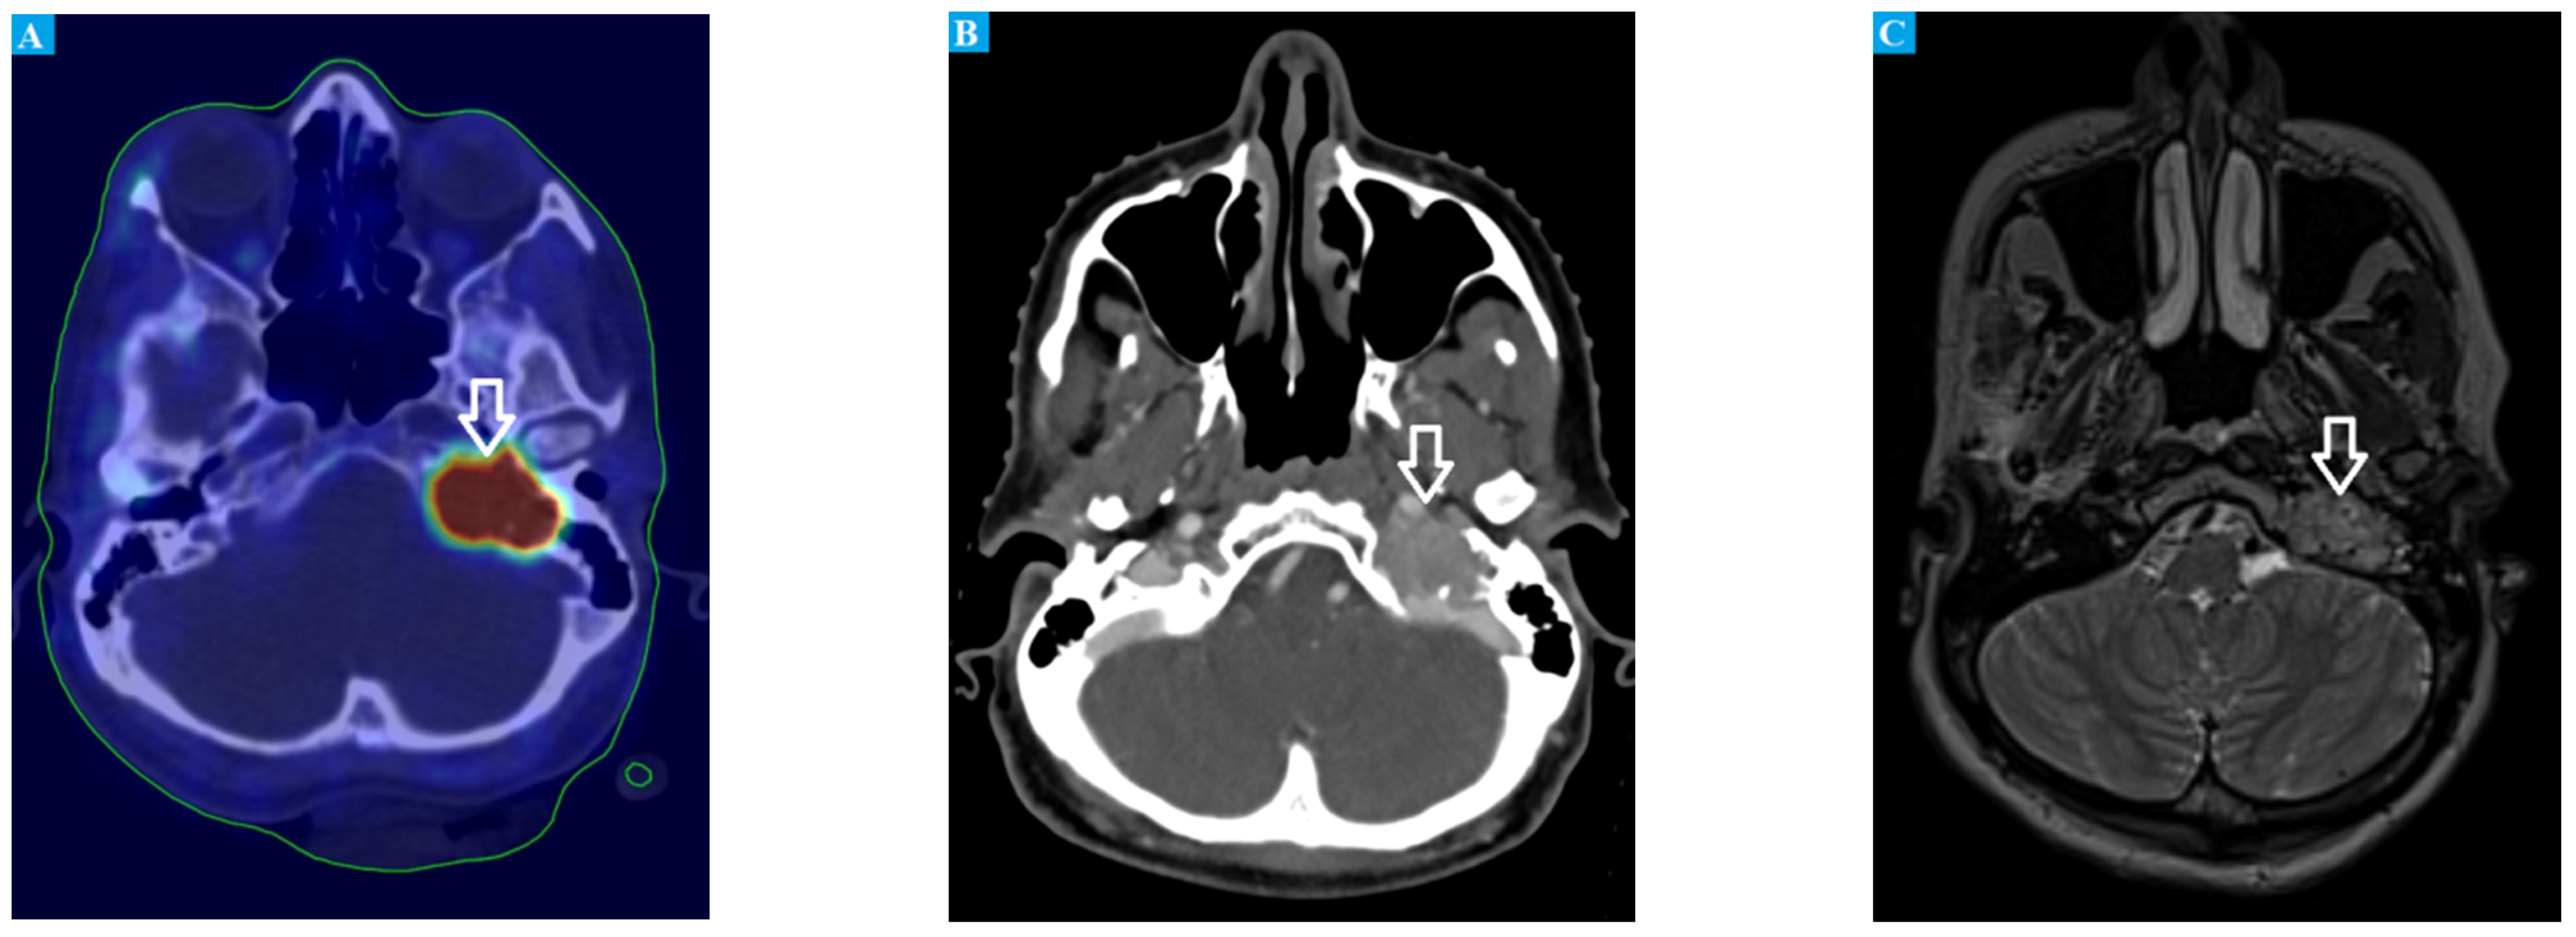

3. Genetic Background

4.2. Imaging